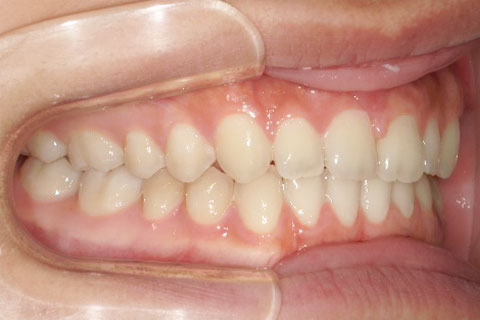

主訴:隙間が気になる

診断名:上顎正中離開

症状:上顎正中離開

患者プロフィール:北九州市・小倉北区30代女性

治療方針:非抜歯矯正治療

治療装置:マウスピース型矯正治療(インビザライン)

抜歯:無し

治療期間:8か月

通院回数:12回

リテーナー: 上顎プレートタイプリテーナー 下顎フィクスタイプリテーナー

治療費用:検査診断料(20,000)+装置料金(500,000)+管理調整料(40,000) +装置撤去時診断料(10,000) +保定装置料金(20,000)=580,000(消費税込)

リスク副作用:痛み・治療後の後戻り・歯根吸収・歯髄壊死

詳しい症例説明: この患者さんは隙間が空いていることを気にされて来院されました。マウスピースタイプの矯正装置で短期間で治療を終えることができました。インビザライン(マウスピース矯正治療)で矯正治療を行うことで治療中も快適に生活できたとのことです。